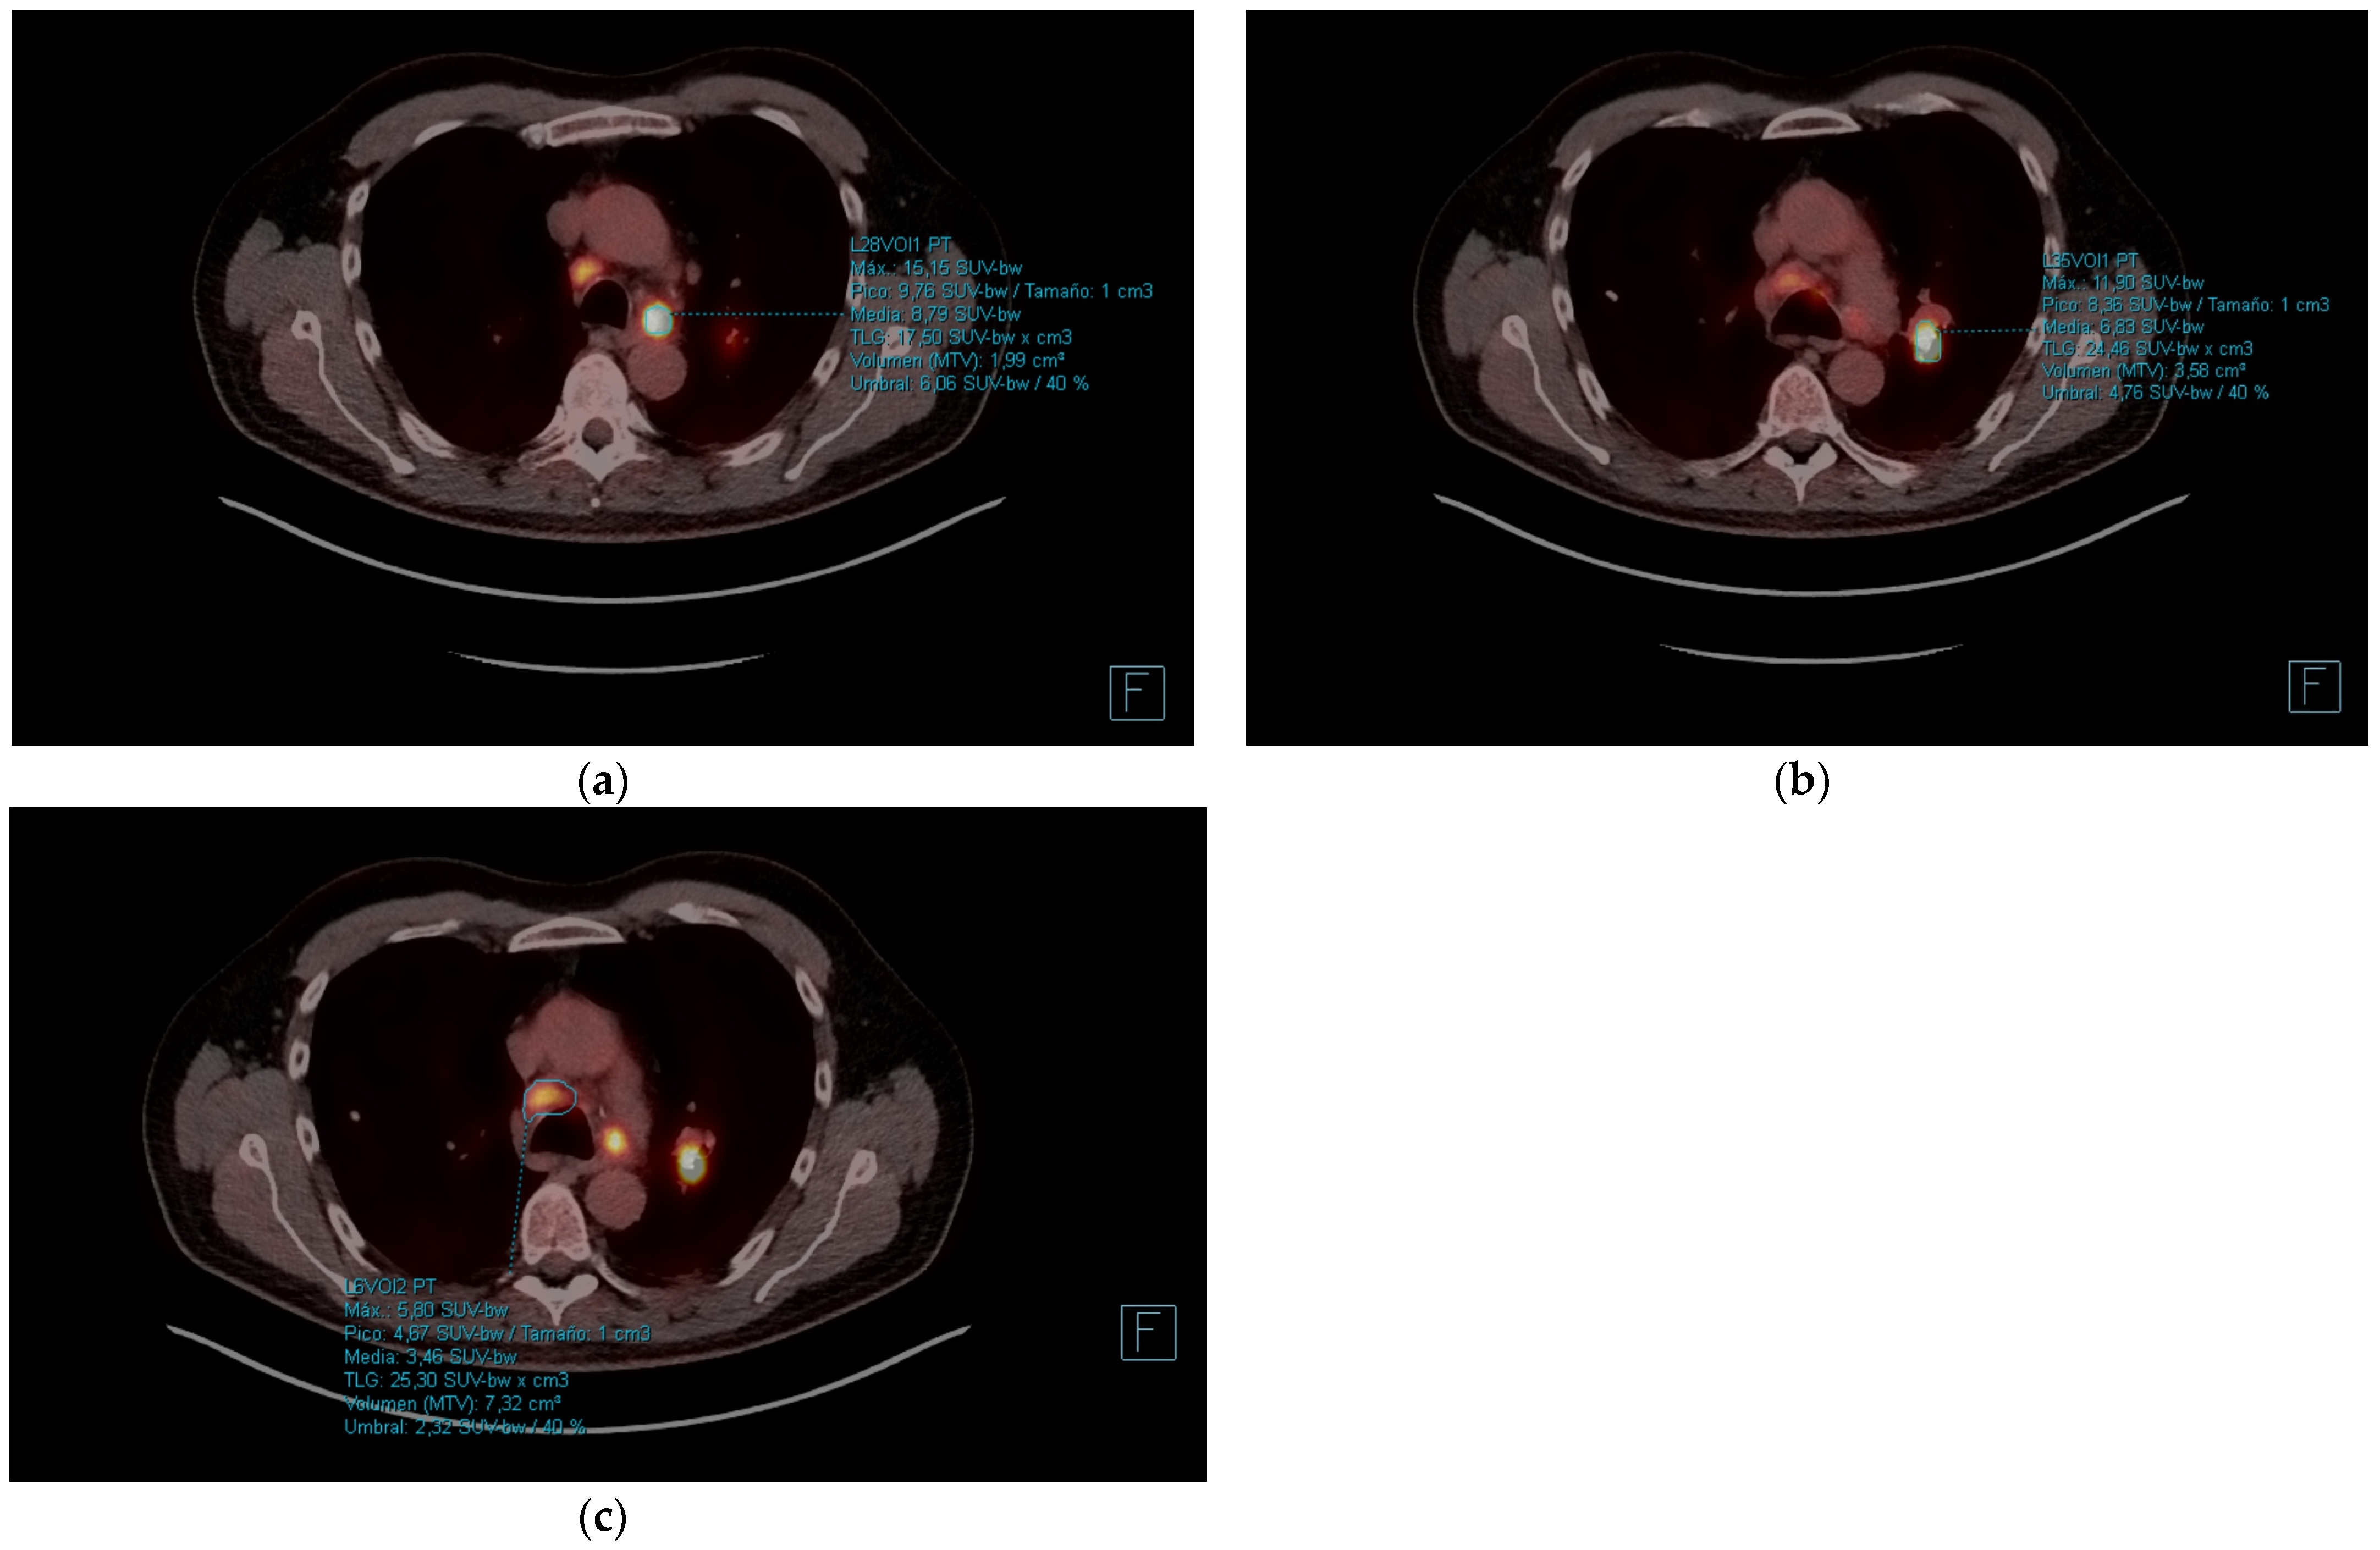

| PET-CT | March 2021 | Initial diagnosis, staging | - Hilar adenopathy compatible with malignancy (SUVmax 20.7). - Hypermetabolic mass (SUVmax 18.3) in the left lower lobe measuring 3.2 × 5.1 cm compatible with malignancy. - Calcified granuloma in right upper lobe. - Abdomen without foci of pathological uptake. |

| PET-CT | October 2021 | Re-evaluation | - Hypermetabolic mass (SUVmax 24.72) in left lower lobe of 4.2 × 3.5 cm. - Complete response of the hilar adenopathies, without pathologic uptake. - Focal increase of FDG in pseudonodular formations in mesenteric fat, up to SUVmax 12.48, in relation to mesenteric panniculitis. |

| PET-CT | October 2022 | Re-evaluation | - Morphometabolic progression of pathologic adenopathies observed on staging PET in March 2021 that had normalized in October 2021, SUVmax 19.5. - Complete morphometabolic response of primary left lower lobe neoplasm, currently 1.8 cm and SUVmax of 2.6. - Signs of mesenteric panniculitis, with practical metabolic normalization of the FDG uptake foci at this level that were visualized in the previous PET scan of Oct/21. |

| PET-CT | April 2023 | Severe abdominal pain that had consulted 4 times in the emergency room | - Hypermetabolic persistence of adenopathies in the right cervical chain, lower paratracheal and right pulmonary hilum with dissociated response, some have progressed and others have improved. - Signs of mesenteric panniculitis, visualizing increased pseudonodular formations, several with FDG uptake up to SUVmax 7.50, not present in the previous study. |